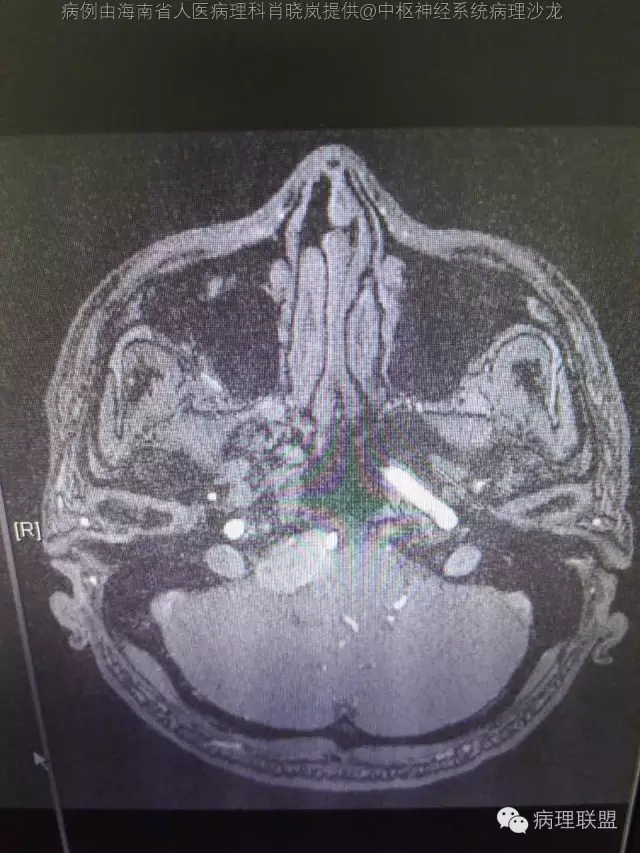

男,36岁。右面部麻木1月余。手术所见:右CPA区见5Ⅹ4cm肿块,灰褐色,血供丰富,质韧,界清。临床诊断:右侧桥小脑角区占位:脑膜瘤。大体检查:灰黑色碎组织一堆,大小2.5Ⅹ2.5x0.5cm,免疫S100,HMB45阳性。Ki67指数低。(病例由海南省人医病理科肖晓岚提供,致谢!)

@海南省人医病理科肖晓岚 影像也是符合黑色素相关肿瘤,可请影像专业的老师分析一下CT结合MR对产生黑色素的病变还是具有一定的特征性的,本例黑色素含量似乎不太多,所以跟脑膜瘤差不太多了,需要请影像老师分析!